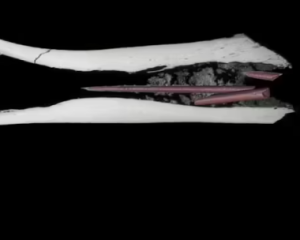

Рентгенівське дослідження виявило несподівану деталь. Усередині порожнини кісткового мозку знаходилися три наконечники стріл, виготовлені з кістки. Це відкриття залишило більше запитань, ніж відповідей, пише The Conversation.

Комп'ютерна томографія показала цікаві результати. У центрі кістки були три наконечники стріл, вкриті токсичною речовиною. Аналіз підтвердив, що це найдавніша з відомих багатокомпонентних отруєних стріл.

Дослідження виявило складний рецепт, який включав щонайменше два рослинних токсини. Також були ознаки третьої отруйної речовини, походження якої ще належить з'ясувати.

Аналіз хімічного складу показав наявність дигітоксину та строфантидину. Це потужні токсини, які використовувалися для полювання. Рослини, що містять ці сполуки, не ростуть поблизу Печери Крюгер. Це свідчить про можливий обмін або транспортування інгредієнтів на значні відстані.